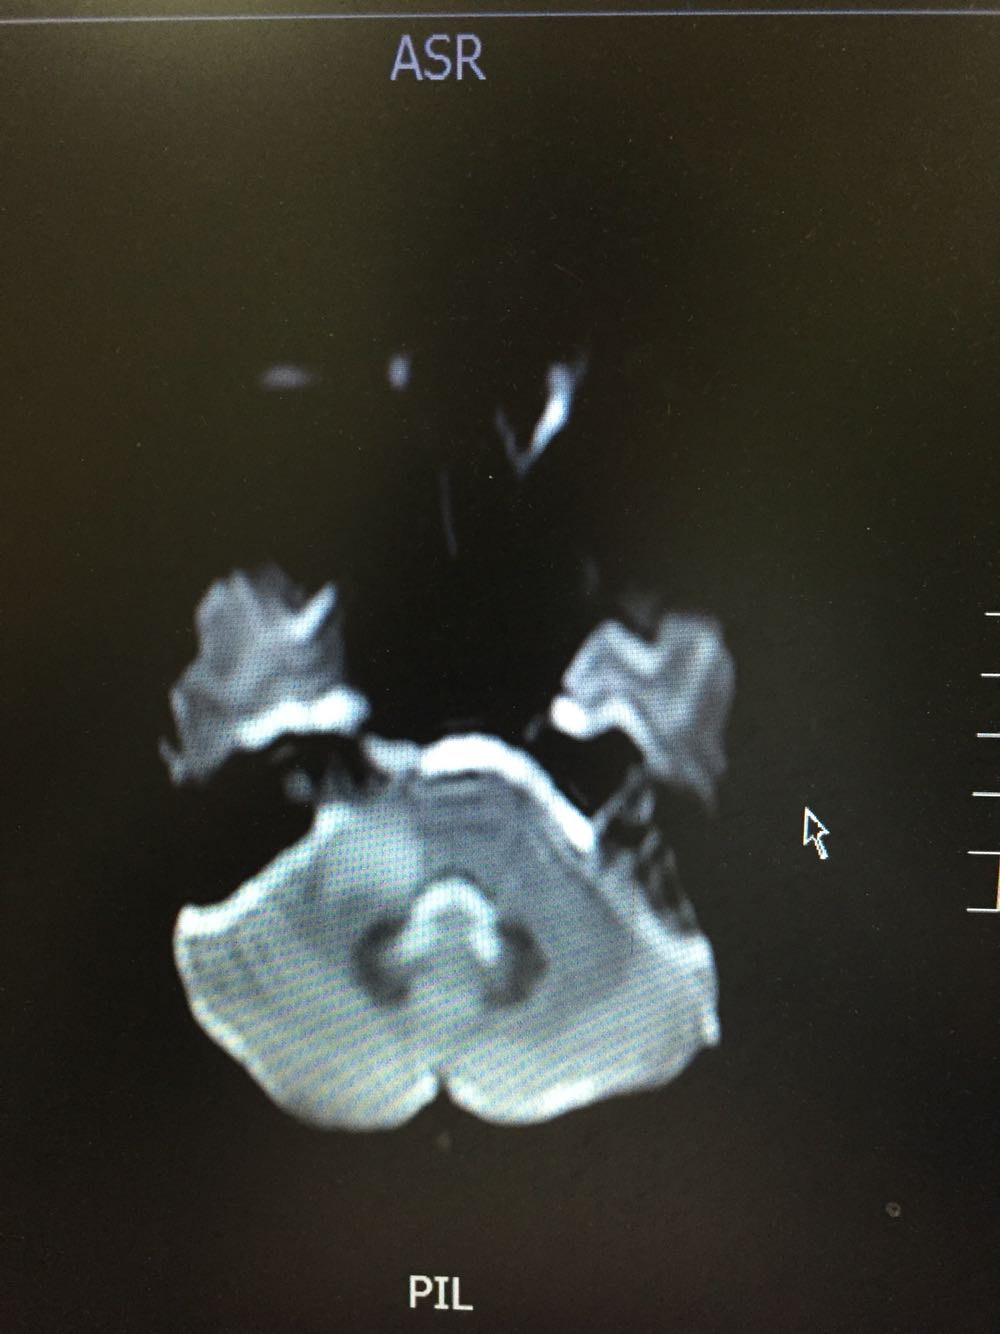

女,35岁,因“右侧肢体无力伴语笨9日”由门诊收入病房。病例特点:1.既往史:青年女患,既往否认高血压病史,否认糖尿病及冠心病史,否认药物、食物过敏史。2.现病史:该患者于入院前9日始出现右侧肢体无力,伴语笨,伴有恶心、呕吐,不伴有头痛,偶有头晕,不伴有尿便障碍,不伴有抽搐发作,为求进一步诊治而来我院。

查体:体温:36。5℃,脉搏:70次/分,呼吸:18次/分,血压:121/79mmHg,神志清楚,言语流利,查体合作,双侧瞳孔等大同圆,对光反射存在,双眼活动自如,鼻唇沟对称,伸舌居中,右侧肢体肌力4级,肌张力正常,腱反射对称,双侧感觉对称,右下肢Babinski征(+)、Chaddock征(+)、颈强(-),克氏征(-)。 脑脊液免疫球蛋白A0.003g/L 抗酸杆菌、墨汁染色阴性,余脑脊液化验未见异常。脑脊液外观无色透明

桥脑脱髓鞘病变可能性大甲强龙冲击治疗

初始考虑青年脑梗死待磁共振增强回报后考虑能否占位可能脑功能成像及脑脊液结果回报后考虑桥脑脱髓鞘病变可能性大,给予甲强龙冲击治疗,冲击治疗后患者症状逐渐好转,右侧肢体肌力出院时5-级。